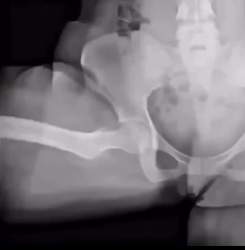

レントゲン動画にできるというやばすぎる最新技術きたよ

いろんなものが解決する

動かせるのはわかったけど正しいんですかこれ?

AIで動かしてんの?

凄い気もするけど普通に体位変えて撮影するだけで良くないのか

普通に心臓カテーテルとか血管内治療とか動画だけど…

放射線大丈夫なの?